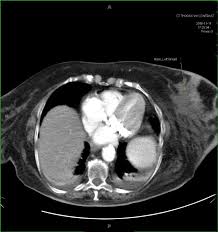

Can A Ct Scan Show Breast Cancer - Best Scans To Detect Cancer Envision Radiology : After detecting the location of the tumor, the area will be biopsied for testing in the lab.. Ct scans are inaccurate for treatment monitoring after cancer treatment, a ct scan is unable to determine whether masses leftover are cancerous: The area covered in the scanning can be determined. Bone scans, positron emission tomography (pet), and computed tomography (ct) all continue to be employed alone or in combination for the detection of breast cancers suspected to have spread. But the risk associated with these tests is worth the benefit, in most cases. A sentinel lymph node biopsy may first be performed to determine whether cancer has spread to the lymph glands under the arm.

The contrast helps to show up areas of increased vascularity and so it does help show up tumours as they have a rich blood supply. Ct scans are inaccurate for treatment monitoring after cancer treatment, a ct scan is unable to determine whether masses leftover are cancerous: Doctors often use this is for cancer staging. When a breast cancer has been diagnosed, some people have a ct scan of their chest and tummy (abdomen) to stage the breast cancer. The specialized cone beam breast ct (cbbct) scanner, developed by boone and colleagues, uses the same amount of radiation as a conventional mammogram.

Knowing the stage helps your doctor decide which treatment you need. So far, researchers at the university have. Doctors often use this is for cancer staging. Mammography is currently the preferred examination for breast cancer screening; During a ct scan, you will be exposed to a small amount of radiation. The area covered in the scanning can be determined. The test has only a limited ability to detect small tumors. The cancer's stage describes the location of cancer, if it spread and if it's changing the function of your organs. A breast pet scan is often very specific and sensitive and is approved for patients. One example is a combined pet and ct scan (known as pet/ct), available in some centers. The specialized cone beam breast ct (cbbct) scanner, developed by boone and colleagues, uses the same amount of radiation as a conventional mammogram. Ct scans can show a tumor's shape, size, and location. The contrast helps to show up areas of increased vascularity and so it does help show up tumours as they have a rich blood supply.

18 F Fdg Uptake Of Bone Marrow On Pet Ct For Predicting Distant Recurrence In Breast Cancer Patients After Surgical Resection Ejnmmi Research Full Text from media.springernature.com Can a ct scan pick up breast cancer. Pet scans are not used to screen women for breast cancer. The test has only a limited ability to detect small tumors. The cancer's stage describes the location of cancer, if it spread and if it's changing the function of your organs. Doctors often use this is for cancer staging. Ct scans can show a tumor's shape, size, and location. When a breast cancer has been diagnosed, some people have a ct scan of their chest and tummy (abdomen) to stage the breast cancer. Bone scans, positron emission tomography (pet), and computed tomography (ct) all continue to be employed alone or in combination for the detection of breast cancers suspected to have spread.

Doctors often use ct scans to help them guide a needle to remove a small piece of tissue. Some fear that the ionizing radiation emitted from ct scans can harm dna and cause tumors. A sentinel lymph node biopsy may first be performed to determine whether cancer has spread to the lymph glands under the arm. When a breast cancer has been diagnosed, some people have a ct scan of their chest and tummy (abdomen) to stage the breast cancer. This helps determine whether or not the cancer can be removed with mastectomy. Ct scans are inaccurate for treatment monitoring after cancer treatment, a ct scan is unable to determine whether masses leftover are cancerous: This can allow for examination of neighboring organs and structures like lymph nodes to check for any signs of disease. This is an excellent way to take a needle biopsy for inflammatory breast cancer because imaging can show the best place to take the biopsy. In some cases, physicians use all three imaging techniques. Bone scans, positron emission tomography (pet), and computed tomography (ct) all continue to be employed alone or in combination for the detection of breast cancers suspected to have spread. It's an effective imaging test for finding cancer and learning its stage. How do ct scans work? The contrast helps to show up areas of increased vascularity and so it does help show up tumours as they have a rich blood supply.

Breast Mri Fact Sheet Westmead Bci from www.bci.org.au The ct scan might show signs of cancer, but that cancer might not be active for example, it could be scar tissue left over from cancer killed off by your treatment Once doctors know where to look, further evaluation can be done with other techniques. This test is most often used to look at the chest and/or belly (abdomen) to see if breast cancer has spread to other organs. The cancer's stage describes the location of cancer, if it spread and if it's changing the function of your organs. Breast pet scans are known as positron emission mammography (pem). The benefits of having a ct scan usually outweigh the risks. During a ct scan, you will be exposed to a small amount of radiation. When a breast cancer has been diagnosed, some people have a ct scan of their chest and tummy (abdomen) to stage the breast cancer.